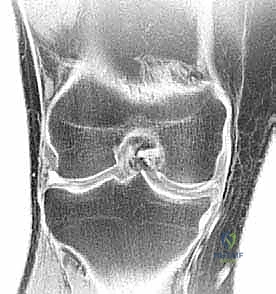

- التصوير بالرنين المغناطيسي (MRI): هو المعيار الذهبي (Gold Standard) لتشخيص تمزقات الغضروف الهلالي. يوفر صوراً ثلاثية الأبعاد وعالية الدقة للأنسجة الرخوة. من خلال الرنين، يستطيع الدكتور هطيف تحديد نوع التمزق، حجمه، موقعه (في أي منطقة دموية)، وما إذا كانت هناك إصابات مصاحبة (مثل تمزق الرباط الصليبي الأمامي ACL).